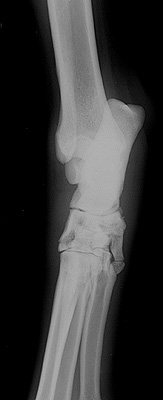

Radiograph of the Dorsopalmar view

Figure 2: Dorsopalmar view